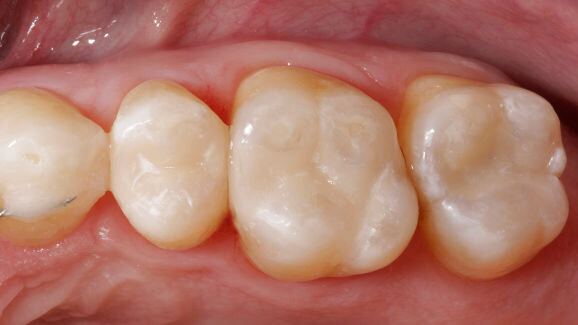

SOUTH BEND, Ind., USA: As reported by the dental manufacturer Heraeus USA, its composite Venus Diamond and Tetric EvoCeram (Ivoclar Vivadent) have achieved equally satisfying results in a new study conducted by German researchers. In the study, almost 98 percent of the tooth restorations done with these composite materials were rated as either excellent or acceptable by independent dentists.

The 18-month in vivo clinical study was conducted by researchers at the Dental School of the Ludwig Maximilians University of Munich, Germany. They compared the clinical efficacy of Heraeus' Venus Diamond composite (VD) in posterior direct composite restorations with that of Ivoclar Vivadent's Tetric EvoCeram composite (TE).

In the study, three dentists placed 48 VD and 50 TE restorations in Class I and II cavities in 71 patients.

According to Heraeus, 97.8 percent of the VD and 97.1 percent of the TE restorations were rated as clinically excellent or acceptable.

Statistical tests revealed no significant difference between VD and TE concerning failure rates. One VD and one TE restoration had to be replaced before the 18-month recall. All teeth were sensitive and none of the patients reported postoperative symptoms. VD displayed a significantly better surface texture compared with TE.

According to the manufacturer, VD is a nano-hybrid universal composite that has low shrinkage stress and strength properties and can adapt easily to the color of the tooth. The material is produced using a special diamond formula, which is based upon silica nanoparticles. Several in vitro and in vivo studies have been conducted on VD in recent years in North America, Asia and Europe, with satisfying results overall.